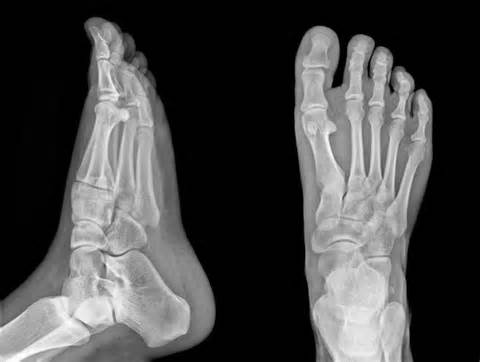

Which is how, on Wednesday morning, I found myself staring at a set of X-rays trying to process the fact that I’ve have two stress fractures in my right foot: little tiny chunks of bone that have broken off from the mother ship and are just hanging out at the edge of my ankle joint.

“We’ll know more once we get the radiology report,” the doctor told me. “But this is an old injury that didn’t heal properly.”